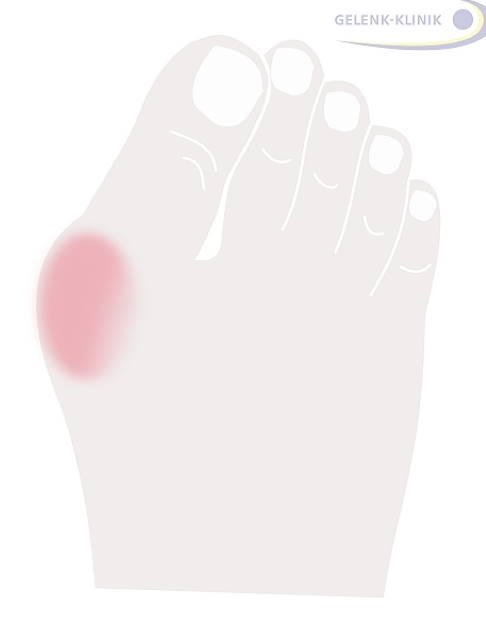

Dabei neigt sich der große Zeh in Richtung Fußaußenrand. Am Großzehengrundgelenk (Metatarsophalangealgelenk) tritt beim Hallux valgus das oft schmerzhaft entzündete und geschwollene Mittelfußköpfchen hervor und drückt gegen den Schuh. Die Großzehensehne verläuft beim Hallux valgus ebenfalls nicht mehr gerade durch das Großzehengrundgelenk. In Deutschland leiden 23 % der 18- bis 65-Jährigen und mehr als 35 % der über 65-Jährigen unter einem Hallux valgus.

- Das Großzehengrundgelenk ist gerötet, geschwollen und schmerzt.

- Patienten klagen über Druckschmerzen, vor allem an der Innenseite des Zehenballens.

Beschwerden in Verbindung mit Hallux valgus treten meist oberhalb des Großzehengrundgelenks auf. Dieses Gelenk tritt oft stark hervor und reibt am Schuhinnenrand. Dadurch entzündet es sich leicht. Der Zehenballen ist beim Hallux valgus gerötet und geschwollen. Im fortgeschrittenen Stadium können sich die Kleinzehen zu Hammerzehen oder Krallenzehen verformen.